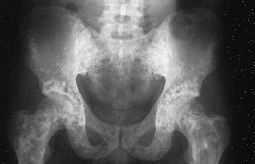

Para descartar una enfermedadsistematizada (por ejemplo, metástasis osteocondensantes) serealiza un estudio radiológico esquelético donde seencuentran imágenes similares de moteado irregular a nivelde muñecas y manos (fig. 2), pies (fig. 3), y rodillas (fig.4).

Figura3.